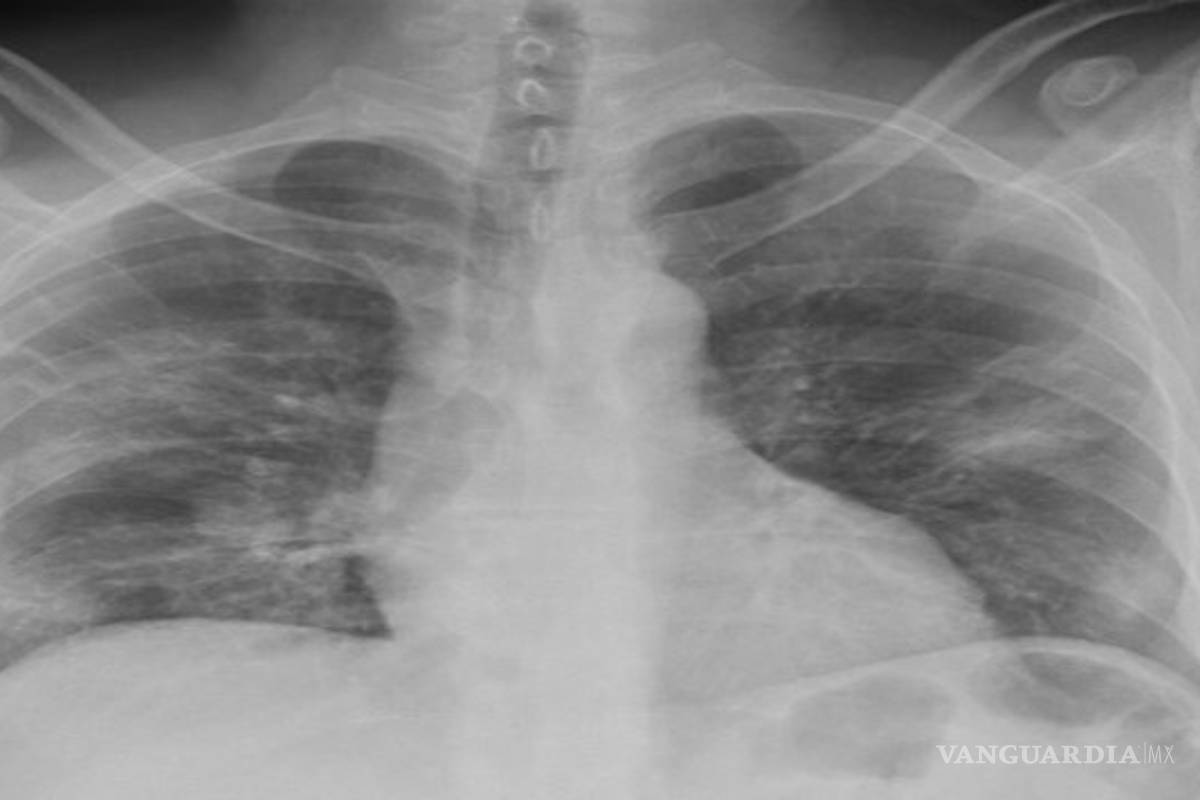

Usuarios de redes sociales lograron posicionar el hashtag de 'neumonía atípica' luego de que se afirmara que en Nuevo León están registrando casos de coronavirus (COVID-19) como otra enfermedad.

El periodista Ciro Gómez Leyva informó el jueves que especialistas de Nuevo León afirmaron que les han ordenado diagnosticar como neumonías atípicas los casos de coronavirus en la entidad.

Casos de muertes por neumonía Cabe mencionar que van dos fallecimientos por un cuadro de neumonóa atípica en Monclova, Coahuila y otros cuatro pacientes permanecen hospitalizados en diversos nosocomios por la misma sintomatología y las autoridades médicas no han brindado información a los famliares de los pacientes sobre el motivo que ha provocado el deterioro de su salud.

La hija de uno de los pacientes denunció recientemente que las autoridades de la Clínica 7 del Seguro Social no les han informado si el paciente padece inlfuenza o COVID-19.

"No nos han querido decir que es lo que tiene, ni los enfermeros quieren entrar a verlo y eso nos duele, ni a nosotras, sus hijas, nos dejan verlo y a mi mamá ya la tienen aislada con él. Queremos un dictamen exacto porque no dijeron si tenía influenza o COVID-19".